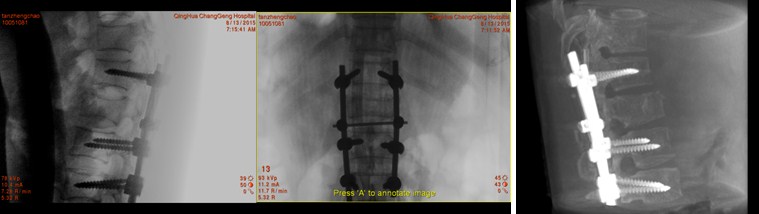

椎弓根内固定后,O-arm扫描见螺钉位置好,左图和中间图为侧位和正位片,最右图为3-D重建图。